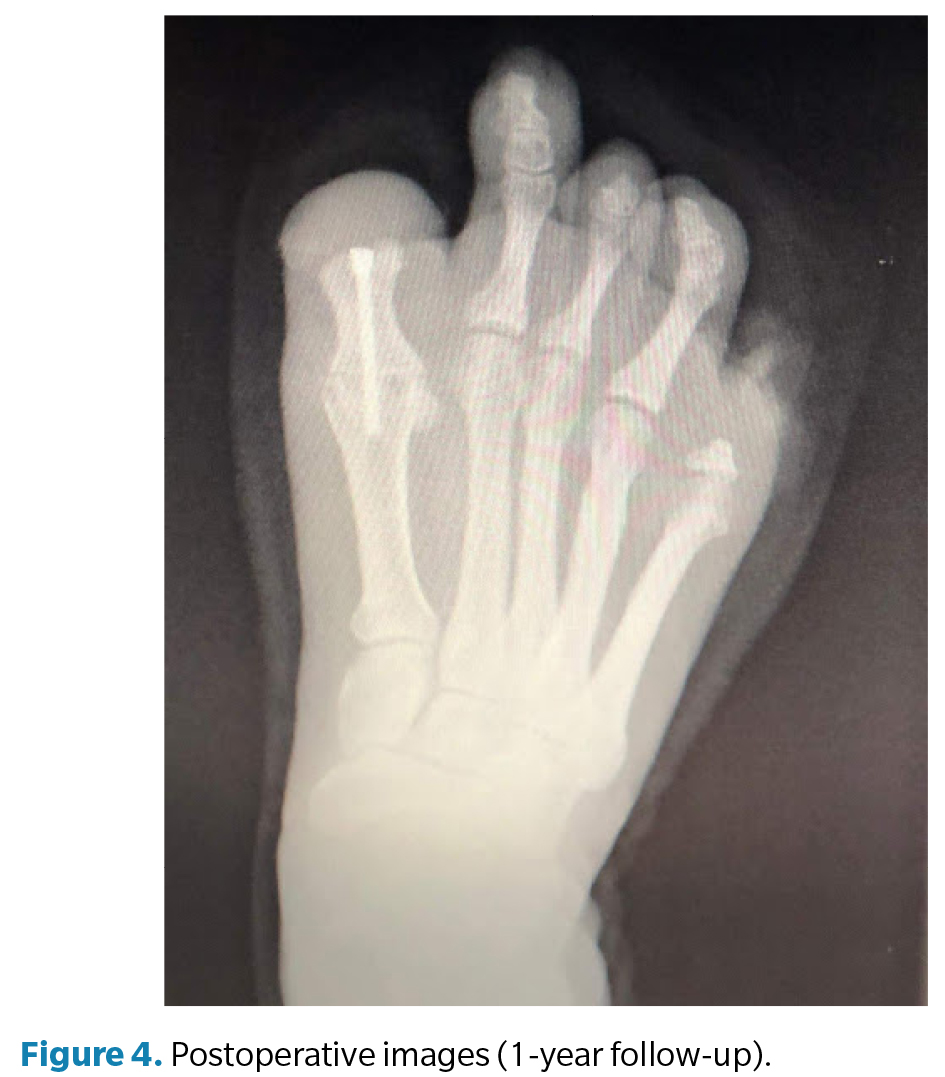

La cirugía (Figura 3) se realizó en marzo de 2022 bajo anestesia regional mediante bloqueo poplíteo posterior con sedación consciente supervisada por anestesiólogo. Se administró profilaxis antibiótica con cefazolina 2 g por vía intravenosa 30 min antes de la incisión y se utilizó torniquete neumático a nivel del tobillo, con presión controlada (a 250 mm Hg) y tiempo de isquemia limitado a 45 min. Se efectuó un abordaje dorsal longitudinal sobre la primera articulación metatarsofalángica, respetando las estructuras neurovasculares. Se identificaron los restos óseos irregulares de la falange proximal y se realizó su resección completa, seguida de remodelado de los márgenes óseos hasta obtener superficies regulares y viables. Posteriormente, se prepararon las superficies articulares de la primera metatarsofalángica mediante fresado y curetaje hasta lograr una base sangrante adecuada para la artrodesis. La posición de fusión se determinó intraoperatoriamente mediante pruebas de carga, fijando el hallux en aproximadamente 10° de dorsiflexión respecto al plano del suelo, con el fin de optimizar la propulsión y evitar la sobrecarga plantar en el muñón residual. La fijación definitiva se realizó con 1 tornillo canulado tipo Herbert, verificándose estabilidad intraoperatoria y correcta alineación mediante fluoroscopia (Figura 4). El procedimiento concluyó sin incidencias, con hemostasia cuidadosa y cierre por planos.

El postoperatorio incluyó curas secas periódicas y seguimiento funcional progresivo. A los 3 meses de la intervención se constató resolución completa del dolor y mejoría significativa en la calidad de la marcha. A los 6 meses la paciente presentó recuperación funcional satisfactoria, por lo que se procedió al alta médica temporal. Posteriormente se confeccionaron prótesis digitales de silicona personalizadas para ambos pies, destinadas a mejorar la simetría podológica, la distribución de cargas y la aceptación psicosocial. En el seguimiento a los 12 meses, la paciente se mantenía asintomática, con consolidación radiográfica completa de la artrodesis, alineación correcta del primer radio y marcha estable sin limitaciones, confirmando el éxito funcional del procedimiento.